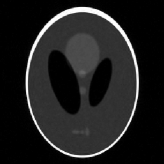

4.1 Phantom experiments

For the piecewise constant phantom experiments, we first compute the fully sampled k-space data using Eq. 3.1 with a piecewise constant function model Eq. 3.6. More precisely, given that ΩjsubscriptΩ𝑗\Omega_{j}’s are ellipses, Eq. 3.6 can be explicitly written as

where J1subscript𝐽1J_{1} is the first kind Bessel’s function of order 111. Then using the variable density random sampling method in [46], we generate 20%percent2020\% undersampled k-space data. The complex white Gaussian noise is also added so that the resulting SNR of the samples is approximately 25dB25dB25\mathrm{dB} (See Fig. 3).

Refer to caption

(a) Fully sampled

(b) Ground truth

(c) Sample mask

(d) Undersampled

Figure 3: Dataset for the phantom experiments. Fully sampled k-space data, its inverse DFT as a ground truth, the undersampling mask, and the undersampled k-space data.